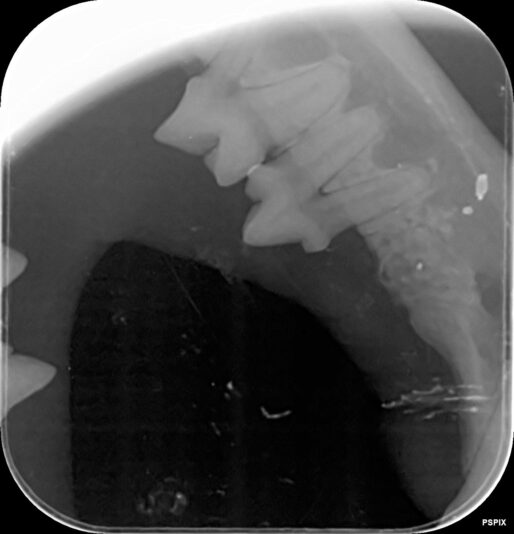

case gegeneraliseerde ontsteking peridontale ruimte

We hebben deze dentale RXen genomen van een jonge oosterse korthaar met chronische gingivitis sinds de geboorte. Op deze Rxen zie ik een verbreed paradontium en een te witte ‘lijn’ bij de aflijning van het alveolair bot. Is er een aandoening die beschreven is bij onze katten en past bij dit beeld? Hoe gaan we verder te werk? Meloxicam lijkt…